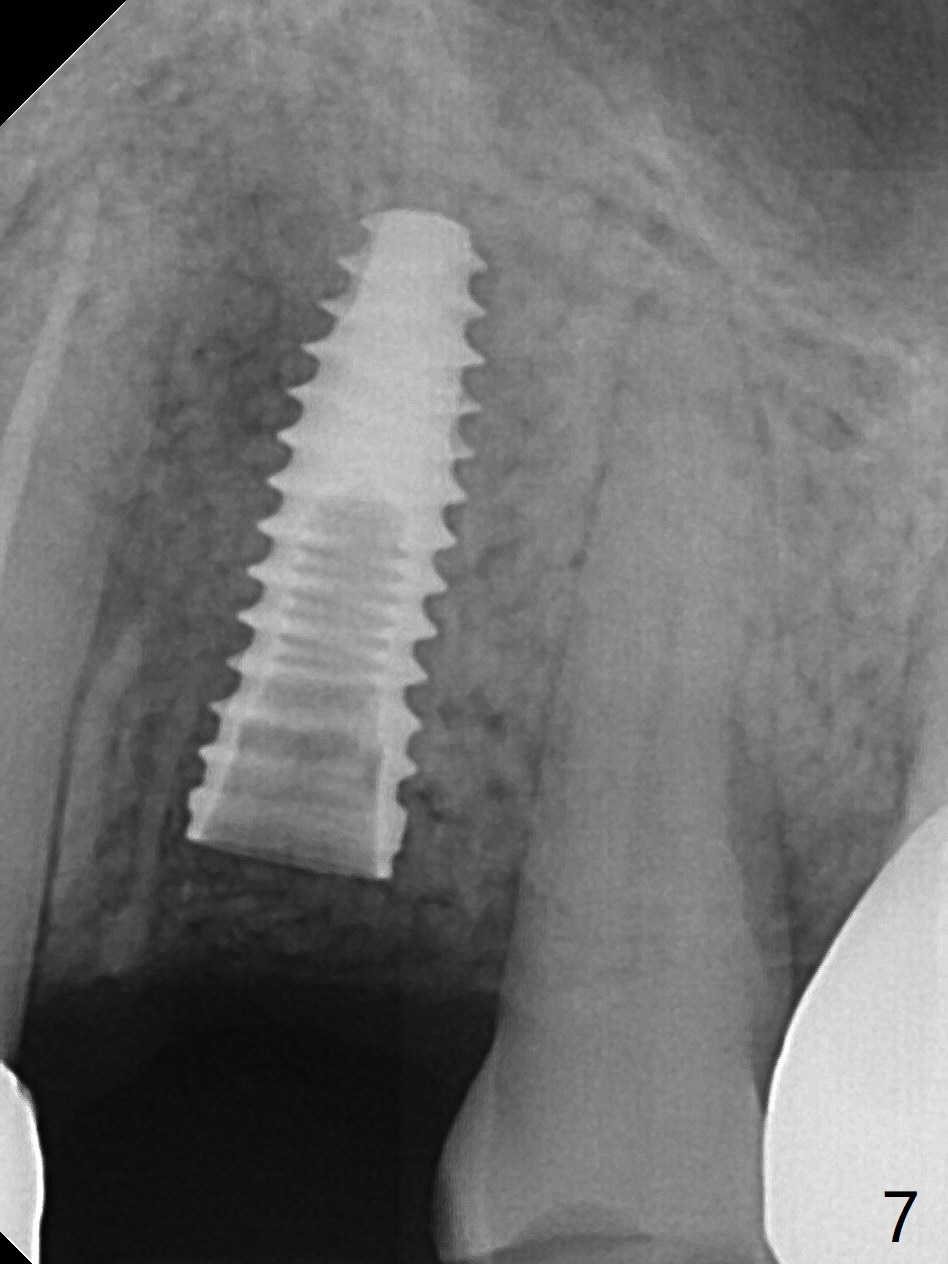

植骨后6个月牙槽窝愈合正常,角化龈和牙槽嵴都宽(图一),导板种植好像不需要切口。利用导板植入,但是离尖牙牙根很近(图二,三)。取出植体后,准备切开改变钻洞方向(图四,五),结果效果不错(图六,七),腭侧骨壁低,安置愈合基台,植骨(图八:*),覆盖胎盘膜,缝合。